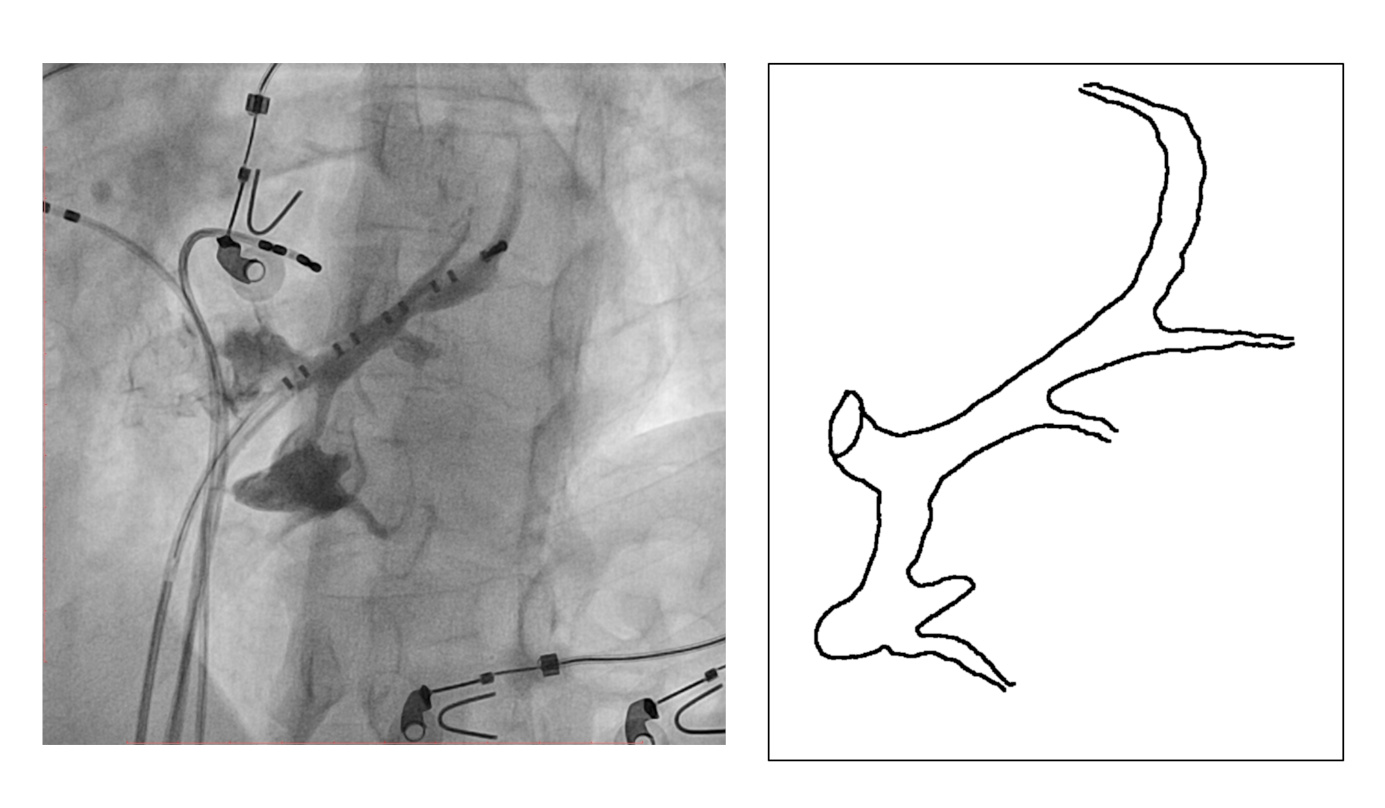

#5 Mapping in diverticulum - CSE potential most important

diverticulum.jpg

med_lat.jpg

signals.jpg